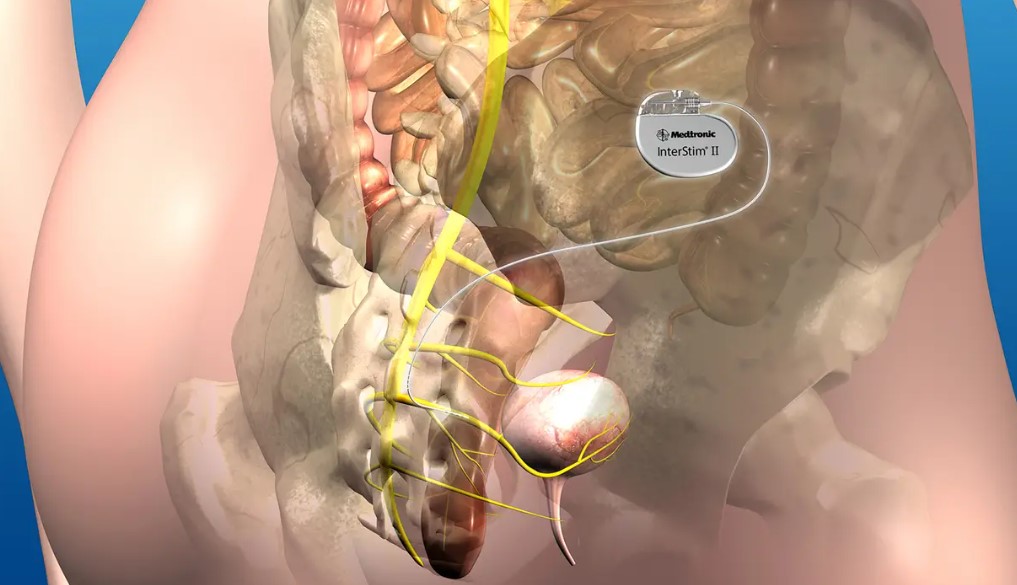

تحریک عصب ساکرال (Sacral Nerve Stimulation) یک روش درمانی نوین است که با ارسال پالسهای الکتریکی به عصبهای ساکرال (S2-S4)، عملکرد عضلات مقعد، روده و مثانه را بهبود میبخشد. این روش شامل:

- قرار دادن یک الکترود در نزدیکی عصب ساکرال

- اتصال الکترود به یک دستگاه تنظیمکننده ضربان الکتریکی

- ارسال پالسهای الکتریکی ضعیف برای تقویت کنترل عضلات کف لگن

- تست اولیه: یک الکترود موقت در نزدیکی عصب ساکرال قرار میگیرد تا پاسخ بیمار به درمان ارزیابی شود.

- در صورت موفقیت تست، کاشت دائمی دستگاه تنظیمکننده پالس انجام میشود.